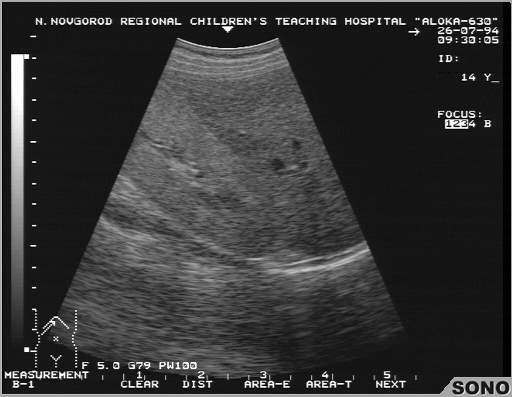

Гломерулонефрит